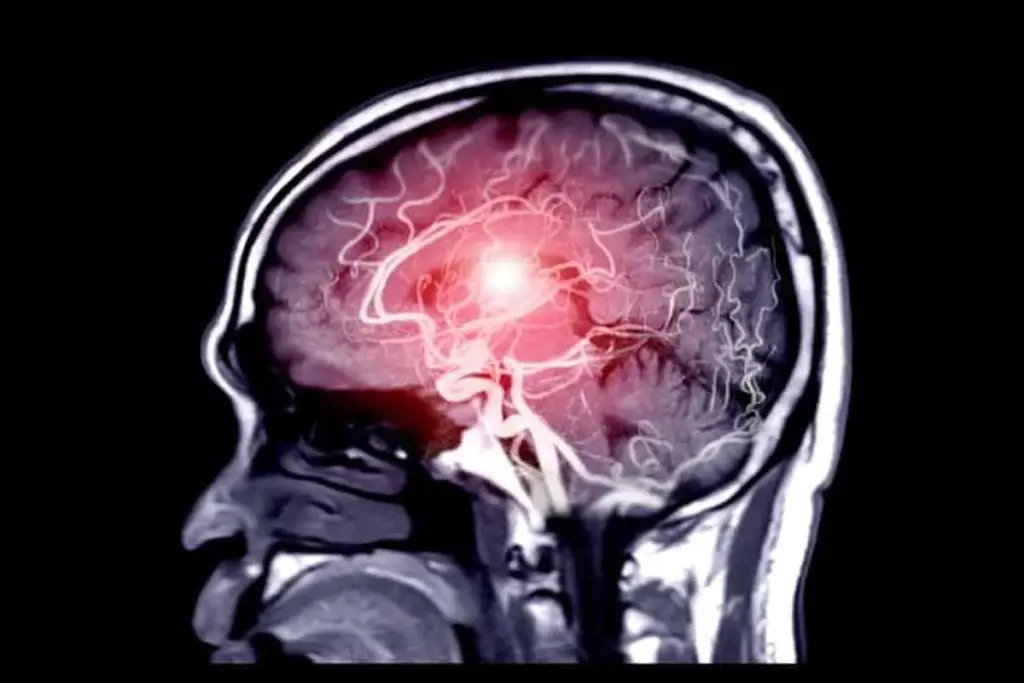

Brain Aneurysm: The Most Common Type

A brain aneurysm is a bulge in a blood vessel in the brain. It can be very dangerous if it bursts, causing a hemorrhagic stroke. Knowing about the different types and where they are located is key for treatment.

Cerebral Aneurysm Definition and Locations

Cerebral aneurysms happen when a blood vessel in the brain weakens and bulges. They can appear in many places in the brain. The Circle of Willis, at the brain’s base, is a common spot for them.

Imaging Techniques

Imaging is key in finding aneurysms. CT scans, MRI, and angiography are top choices. CT scans show detailed views of the body, helping spot aneurysm size and location. MRI gives clear images of blood vessels, aiding in precise diagnosis. Angiography, like digital subtraction angiography, is the best for seeing blood vessels and aneurysm details.